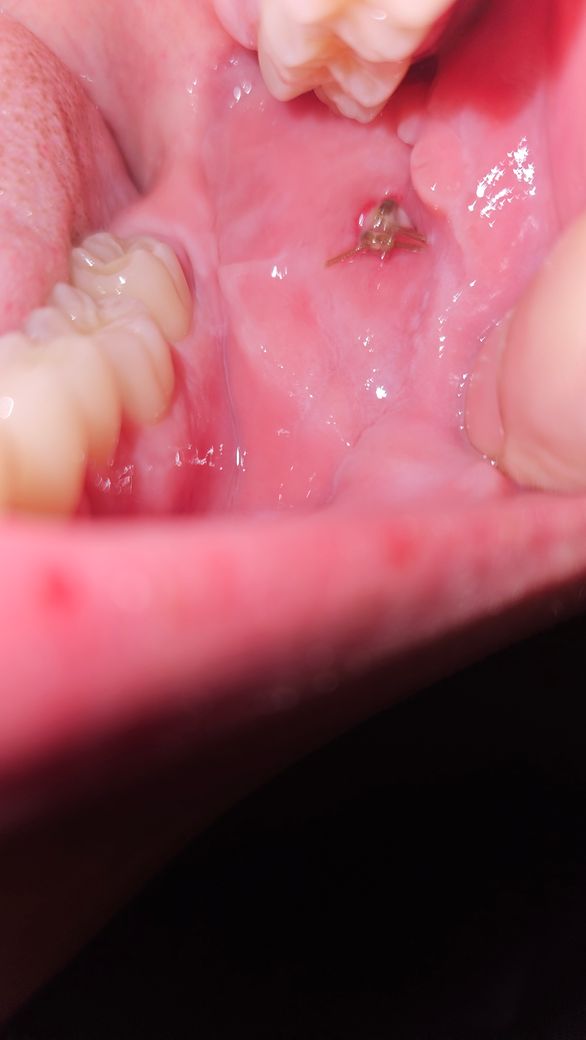

입안 볼쪽인데 염증인가요 이물질인가요 새살인가요?

부위는 입 안에 볼 쪽이구요

이물질같아서 아무리 가글을 해봐도 남아있는데

혹시 염증이거나 새살이 돋는 중인건가요?

절개했다가 다시 봉합해둔 상태입니다

절개해두 부위에 봉합사가 남아 있는 것으로 보입니다. 잇몸은 잘 아물고 있는 것으로 보이나 봉합사를 제거하고 치과에서 진료를 받아보는 것이 좋습니다.

절개하였다가 봉합한 부위에 새로운 살이 나오면서 아물고 있는 것으로 보이기에 억지로 떼어내거나 하지는 않길 권합니다. 염증이 덧나지 않도록 소독용 가글 사용하는 것을 권합니다.